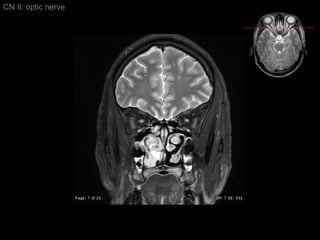

Intraocular segment 1 mm in length Ganglion cell axons exit globe CN II: optic nerve

Intraorbital segment 20-30 mm in length Extended posteromedially from back of globe to orbital apex (within intraconal space) CN2 longer than actual distance form optic chiasm to globe    allowing for eye movement CN II: optic nerve

Intraorbital segment CN II: optic nerve

Intraorbital segment Covered by 3 meningeal layers as brain  Subarachonoid space contains CSF    continue with suprasellar cistern CN II: optic nerve

Intracanalicular Segment Segment within bony optic canal  4-9 mm in length CN II: optic nerve

Intracanalicular Segment CN II: optic nerve Dura of CN2 fuses with orbital periosteum (Periorbita)

Intracranial Segment About 10 mm length from optic canal to chiasm Covered by pia and surrounded by CSF within suprasellar cistern CN II: optic nerve